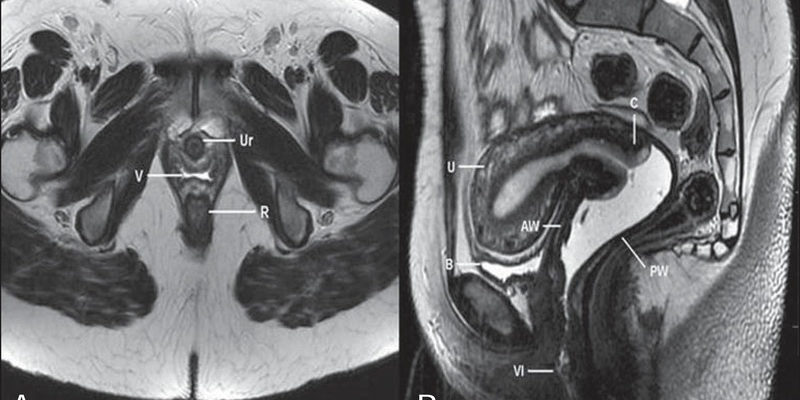

Эта картина изменилась с появлением и применением неинвазивного метода диагностики патологии матки и придатков — магнитно-резонансной томографии. Даже стандартная МРТ способна обнаружить практически все виды патологических процессов в женских половых органах.

При интерпретации МРТ-изображений яичников и органов малого таза определяется наличие или отсутствие структурных изменений тканей. На изображении специалист визуализирует: